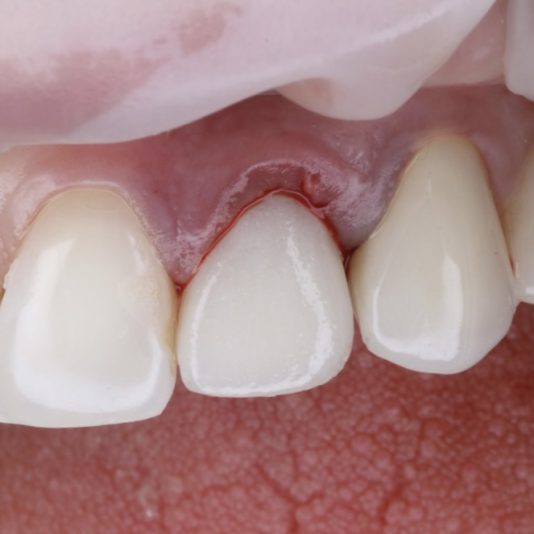

The pilot drill sets the foundation for the entire implant trajectory. If the angulation is even slightly off at this stage, it can result in improper placement, bone perforation, or aesthetic challenges, especially in the anterior region.